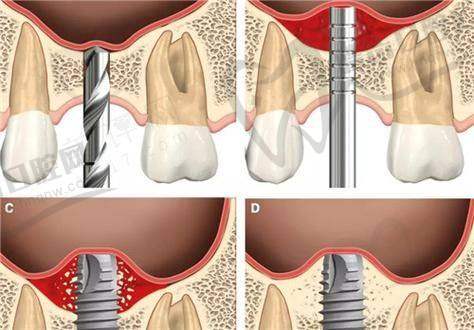

上颌窦提升术后修复期的真实体验

"做完上颌窦提升手术后的15天,是我这辈子更难熬的日子!"这是许多经历过上颌窦提升手术患者的共同心声。作为种植牙手术中的重要辅助步骤,上颌窦提升术虽然技术成熟,但术后修复过程却让不少患者叫苦不迭。那么,为什么上颌窦提升后15天更难熬?这段时期究竟会经历哪些不适?又有哪些注意事项能帮助顺利度过这段修复期?

根据临床数据显示,约65%的患者认为上颌窦提升术后7 - 15天是修复过程中更不舒服的阶段。这段时间内,患者通常会经历肿胀、疼痛、鼻塞、异物感等多种不适症状。而15天这个时间点尤为特殊,因为此时手术创口正处于愈合关键期,但麻醉成效和初期止痛药物作用已基本消失,患者开始真实感受到手术带来的各种反应。